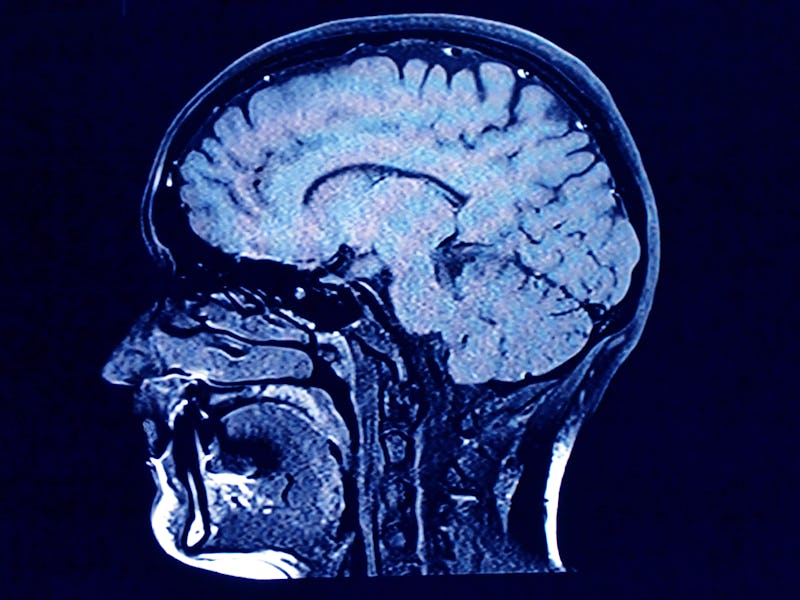

Since the sizzling fried egg in the iconic 1987 Partnership for a Drug-Free America ad, we’ve been asked to think about what a “brain on drugs” looks like. Now, we have a slightly better idea, thanks to a study that used MRI scans of adolescent brains at 14 and again at 18 to paint a picture of one plausible effect of marijuana.

In the JAMA Psychiatry report published Wednesday, that effect boiled down to this: accelerated thinning of parts of the brain called the right and left prefrontal cortices.

The team took MRI scans of the teen’s brains to determine cortical thickness. Then, five years later, the students were asked how many times they estimated they had used cannabis so far, among other questions. Their brain scans were taken again to determine cortical thickness.

OBJECTIVE: To examine the degree to which magnetic resonance (MR) imaging–assessed cerebral cortical thickness development is associated with cannabis use in a longitudinal sample of adolescents.